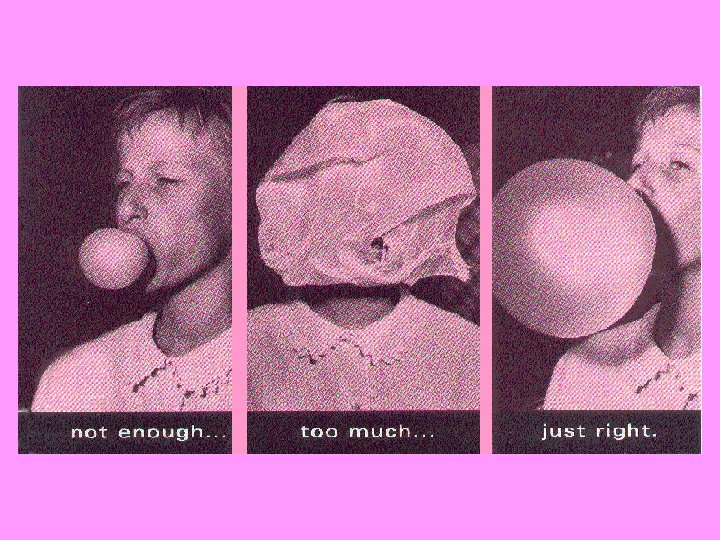

Pressure/Volume http: //www. brighamandwomens. org/respiratorytherapy/Images/ratlung. swf ratlung